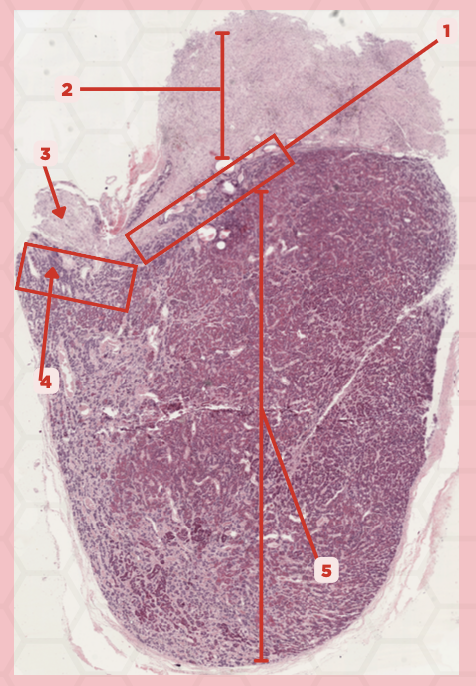

Pituitary

Identify the specimen.

Anterior Lobe

Identify the structure labeled as 1.

Posterior Lobe

Identify the structure labeled as 2.

Intermediate Lobe

Identify the structure labeled as 3.

Pars Tuberalis

Identify the structure labeled as 4.

Pituitary Stalk

Identify the structure labeled as 5.

Neural Ectoderm

What ectoderm is #2  derived from?

Oral Ectoderm

What ectoderm #1, #3, & #4 derived from?